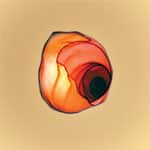

Sesame Elevates Gamma Tocopherol, Inhibits LDLIn 2001, researchers from the University of Hawaii Cancer Research Center tested nine subjects by feeding them muffins containing equivalent amounts of gamma tocopherol derived from sesame seeds, walnuts, or soy oil. Eating muffins containing sesame increased serum levels of gamma tocopherol by 20% in as little as three days. No similar benefit was seen in subjects eating muffins containing gamma tocopherol derived from walnuts or soy oil. All of the subjects who consumed muffins containing sesame seeds had detectable levels of the sesame lignan sesamolin in their plasma. According to the study authors, “consumption of moderate amounts of sesame seeds appears to significantly increase plasma gamma tocopherol and alter plasma tocopherol ratios in humans and is consistent with the effects of dietary sesame seeds observed in rats leading to elevated plasma gamma tocopherol and enhanced vitamin E bioactivity.”18 In another study also conducted in 2001, Swedish women who consumed dietary sesame oil saw their gamma tocopherol levels increase 41% from their pre-supplementation levels—without affecting serum alpha tocopherol concentration.19 This effect could be due to the gamma tocopherol or the lignans present in sesame oil, or the interaction of both. Oxidation of dangerous low-density lipoprotein (LDL) is a primary initiating event in the development of atherosclerosis.20 LDL oxidation occurs when oxidants such as peroxynitrite radical, iron ascorbate, and copper ascorbate modify LDL particles. Once LDL is oxidized, it can no longer be recognized by LDL receptors, but instead is targeted by scavenger receptors on macro-phages, leading to the formation of lipid-filled foam cells observed in atherosclerotic lesions.21 Researchers have found that sesame lignans are highly effective inhibitors of LDL oxidation. In one test designed to measure the ability of various antioxidants to inhibit oxidation, LDL was exposed to a standardized oxidizing agent, such as copper iron ascorbate (CuSO4), and then treated with various antioxidants to determine their potency. Butylated hydroxytoluene, or BHT, is a food preservative that has long been recognized as being among the most potent inhibitors of CuSO4-induced lipid peroxidation. In 1995, researchers at the University of Shizuoka, Japan, found that sesaminol, the most prevalent sesame lignan, effectively inhibited LDL oxidation, outperforming other well-established biological antioxidants, including quercetin, epigallocatechin-3 gallate (EGCG), theaflavin, BHT, and alpha tocopherol. In fact, the lag time to oxidation—the determining factor in antioxidant potency—was greatly increased.22 The lignan sesaminol is thus a strong antioxidant with powerful antioxidant effects.

The isoprostane marker measures the amount of cell membrane damage caused by free radicals. Also called lipid peroxidation, cell membrane damage involves a free radical chain reaction of cell membrane fatty acids. Normally, lipid peroxidation results in one free radical destroying 8 to 10 normal molecules before being quenched. Supplementing with vitamin E products can limit this destruction to one or two molecules rather than the normal 8-10 molecules that occurs without supplementation. Compared to the gamma tocopherol-tocotrienol group, those taking gamma tocopherol plus sesame showed a 22% reduction in serum isoprostane levels after two weeks of supplementation. The PLGF-1 marker is an extremely sensitive new test for atherosclerotic risk in humans. PLGF-1 stands for “placental growth factor” because it was originally identified in the placenta. For adults, however, high levels of PLGF-1 are indicative of atherosclerotic lesions. PLGF-1 stimulates vascular smooth muscle cell growth, recruits macrophages into atherosclerotic lesions, up-regulates production of tumor necrosis factor-alpha and stimulates undesirable angiogenesis. In the animal model, inhibition of PLGF-1 suppressed both atherosclerotic plaque growth and arterial wall inflammatory reactions. PLGF-1 may be considered a marker for the presence of unstable arterial wall plaque. Compared to the gamma tocopherol-tocotrienol group, those taking gamma tocopherol plus sesame showed an 11.5% reduction in serum PLGF-1 levels after two weeks of supplementation. Considering that the subjects in this experiment were a healthy group to begin with—with baseline PLGF-1 levels that were already in the lowest percentage quartile—the 11.5% reduction recorded in the gamma tocopherol plus sesame group was impressive. Presumably, those with arterial wall dysfunction, who normally have high PLGF-1 levels, would derive even greater benefit from supplements that lowered this very sensitive inflammatory marker. The same would hold true for aging adults whose baseline oxidative stress levels are very high compared to this healthy group of test subjects. Based on these three advanced measurements of free radical and inflammatory damage, gamma tocopherol plus sesame lignans is on average 25% more effective in reducing three biomarkers of oxidative stress and inflammation than the more expensive gamma tocopherol plus tocotrienols.